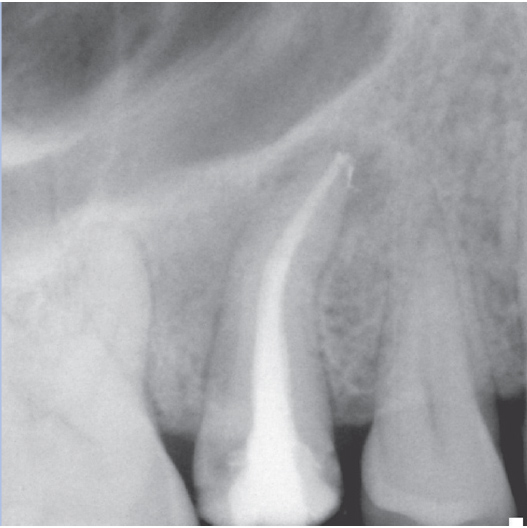

Before

Before Root Canal treatment